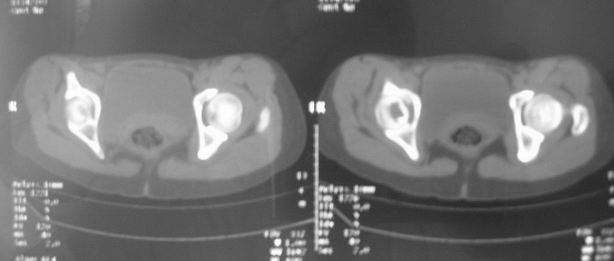

右股骨骨巨细胞瘤

女,31岁,右髋部疼痛半年,加剧两天不能行走

电话追踪:家属告知病人已手术,术后病理骨巨细胞瘤。

拾荒者分析:该病例囊肿透亮度较高,骨膨胀轻微,还是要首先考虑骨囊肿。至于与骨细胞瘤的鉴别,影像鉴别困难。我想,发病年龄及临床症状可能是主要参考点。